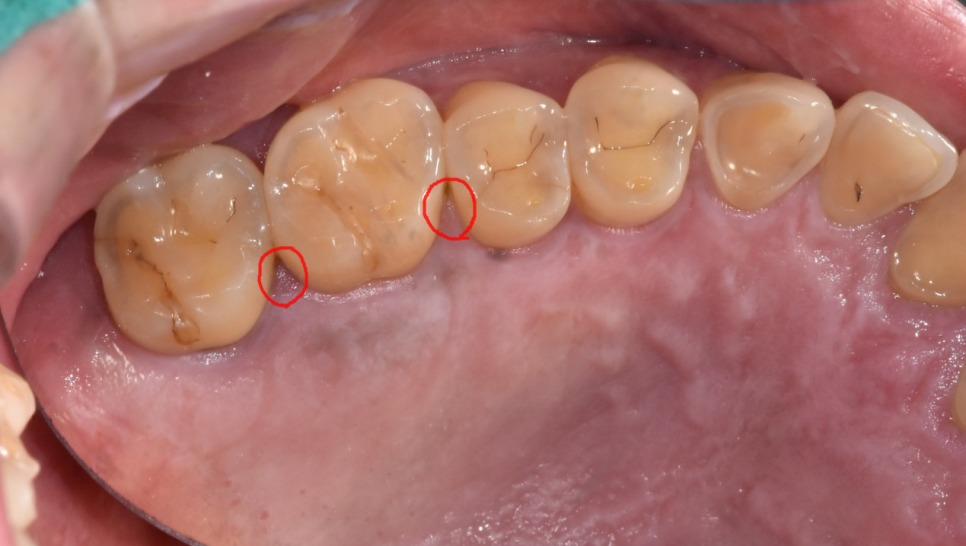

240427 잇몸이 살짝 부은 치은염

여기서 고덕동 치과에서 적절한 치료를 받지 않으면

그 다음 단계인 치주염으로 진행되는데요.

잇몸에 문제가 생긴 것을 넘어

치아를 지탱하는 뼈와 조직까지 영향을 미치는 단계입니다.

치은염 증상은 기본!

잇몸뼈가 녹는다거나

치아의 흔들림

잇몸에서 고름이 나온다거나

치아가 움직이는 증상이 생길 수 있습니다.